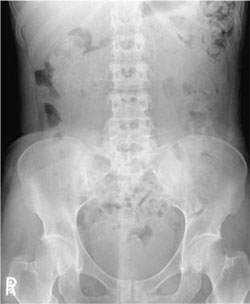

Which structure is evaluated to determine rotation on an AP radiograph of the abdomen?

- Psoas major muscles

- Kidney shadows

- Iliac wings

- Symphysis pubis

Iliac wings

What is the specific positioning error if the right iliac wing is wider in appearance as compared to the left as seen on an AP supine abdomen radiograph?

- Rotation of the right side of the body toward the IR (right rotation)

- Rotation of the left side of the body toward the IR (left rotation)

- Tilt of the spine to the right

- Tilt of the spine to the left

Rotation of the right side of the body toward the IR (right rotation)